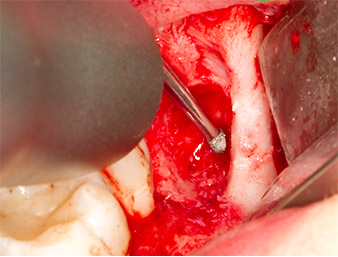

To expose the root remnant with as little trauma as possible to the tissue, a further instrument was used (Piezomed S2) that is primarily indicated for preparing the lateral window in augmentations of the sinus floor. The diamond-coated ball was additionally used to smooth sharp bone edges (Fig. 6 and 7). All the Piezomed attachments were used with the relevant automatic default setting without booster function.

Piezomed S2

Fig. 6: The root remnant is carefully exposed with a diamond-coated spherical instrument (Piezomed S2), bone edges are smoothed.

root remnant 38

Fig. 7: The root remnant 38 (LL8) is well exposed in its alveole for subsequent removal.

Using an instrument for periodontal debridement (Piezomed P1), the periodontal ligament space of the radix relicta was then widened minimally (Fig. 8).

The same activated instrument was inserted into the root canal and loosened the fragment as a result of its micro-oscillating vibrations (Fig. 9, 10).